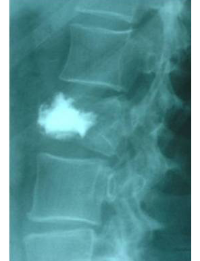

Comparació pre- i post-operatoria d’una cifopastia cementada

Dona, edat 55 anys, fractura aixafament dret de L2

Després 1

Després 2